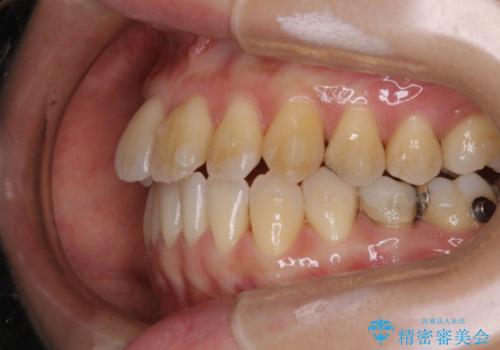

前歯が内側に入っている:インビザライン治療

- 上の前歯は内側に入っていることが気になりご相談にいらした方です。インビザラインにて治療を行いました。

1週間でのマウスピース交換を指示していましたが、20時間以上使えない時があると不安との事で、2週間ごとの交換にしていました(実際はほとんど20時間以上使用できていたようです)。治療終了まで時間はかかりましたが、最終的に綺麗に並べることができ、大変喜んでいただけました。